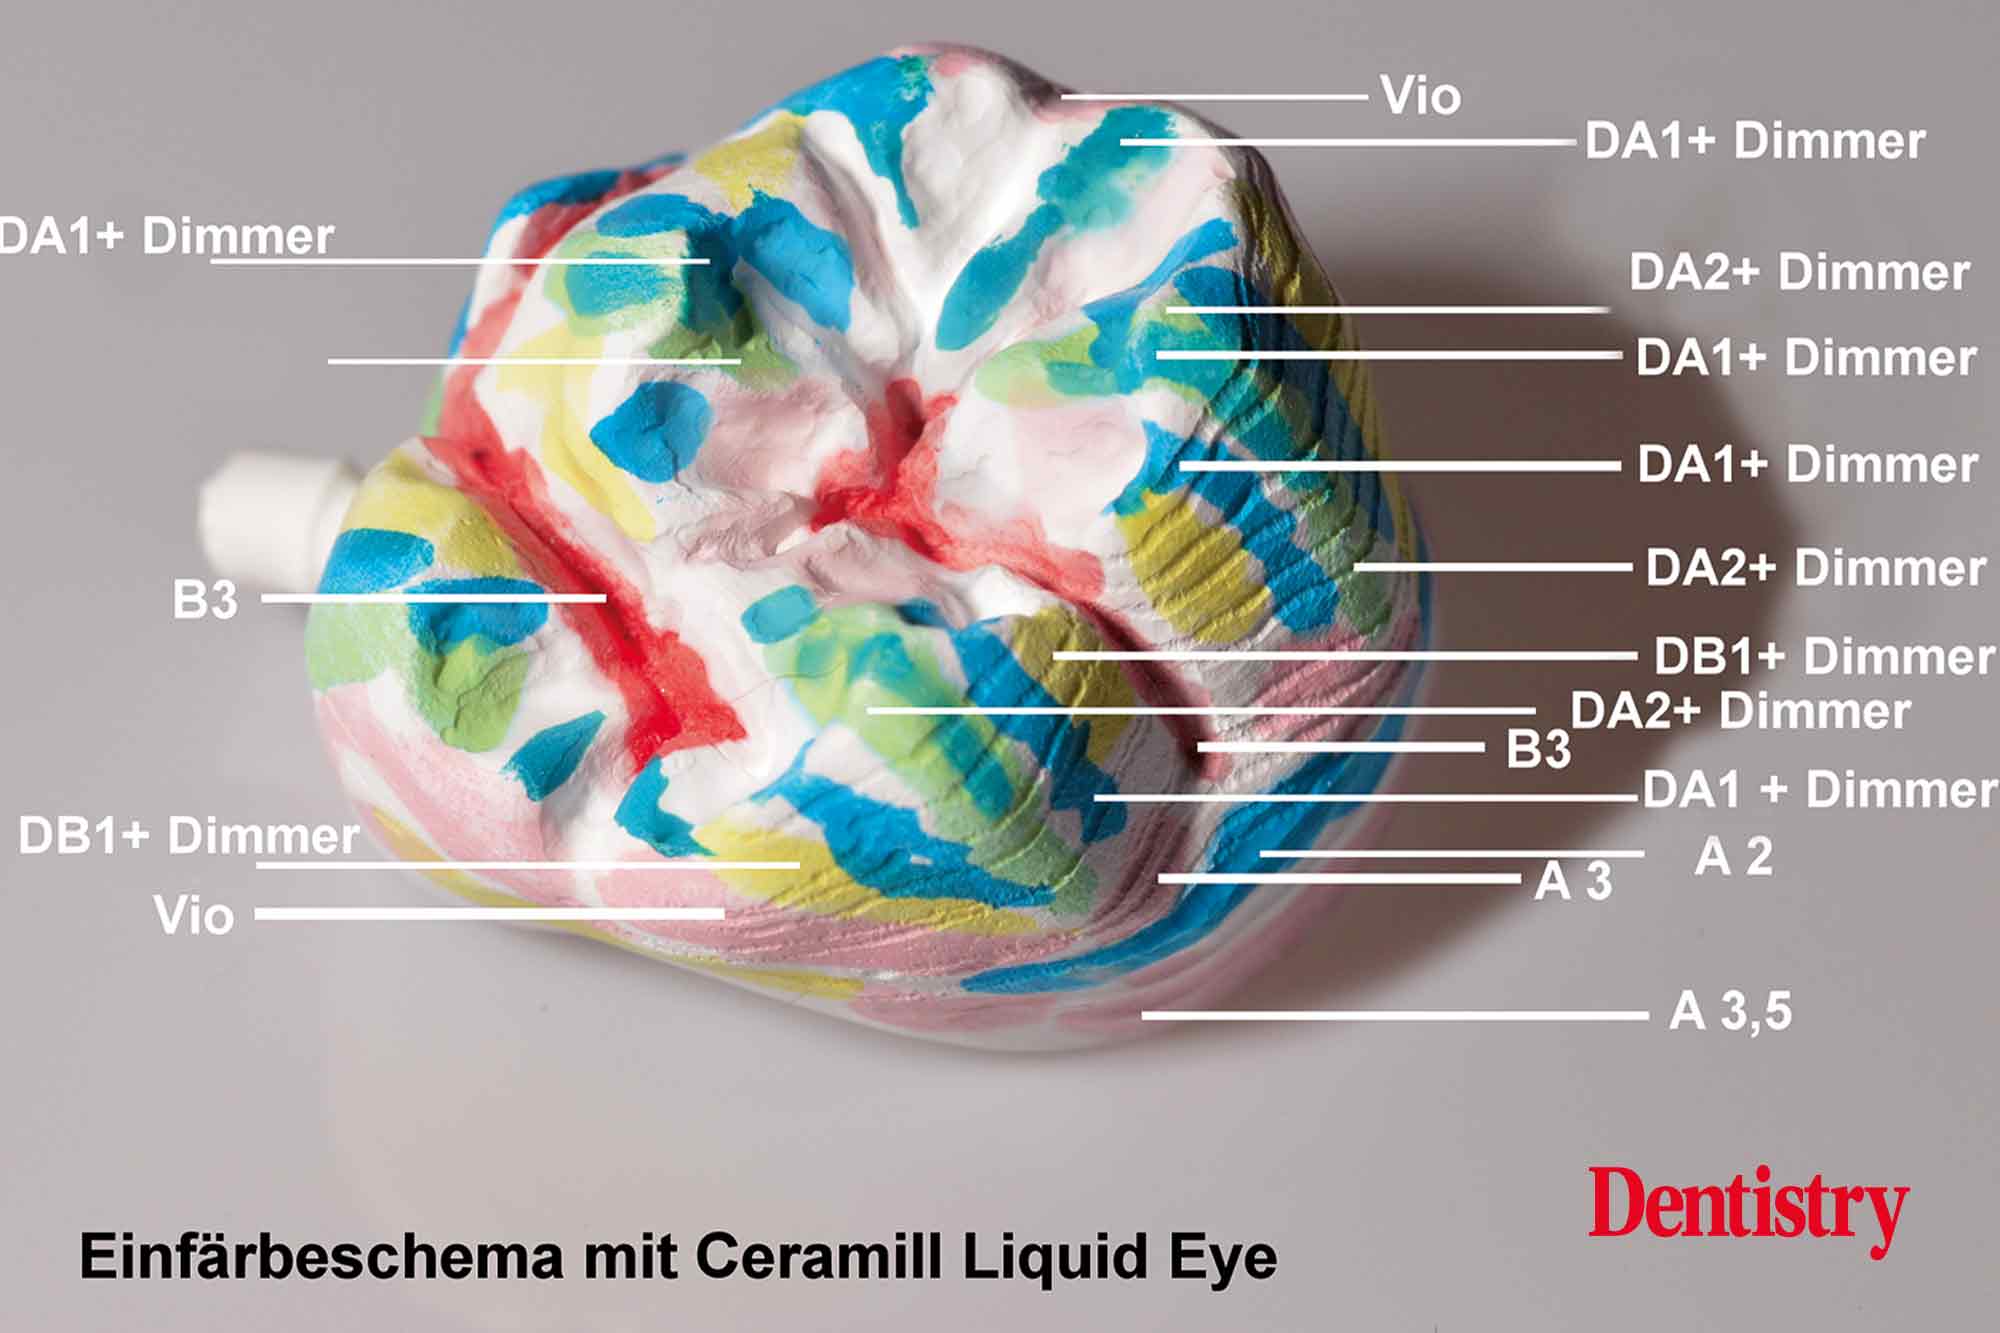

The milled Ceramill Zolid FX (super high translucent) monolithic zirconia maxillary crowns were polished and then individually coloured with brushed-on Ceramill liquid colour before sintering. As opposed to lithium disilicate, it can be coloured before sintering. The advantage of this is that it produces a similar chroma to that of natural teeth.

The colouring liquids were available in all VITA classical shades and were applied in an alternating fashion. Liquid colours Dentin A1 + Dimmer, Dentin A2 + Dimmer, Dentin B1 + Dimmer (30% to 70%) and Violet were applied in a strategic way with dentin colours B3 and A3.5 being used in the fissure and marginal areas (Figures 14 and 15).

The crowns were immersed for 10-15 seconds in the dentine-coloured Ceramill Dimmer liquid.

Depth effect, due to the transparency effect of the Ceramill liquids, was achieved using alternating NB/C/D liquids, brown/orange liquids for fissures and interdental regions, grey/blue shade modifier liquids, and Ceramill Liquid Eye.